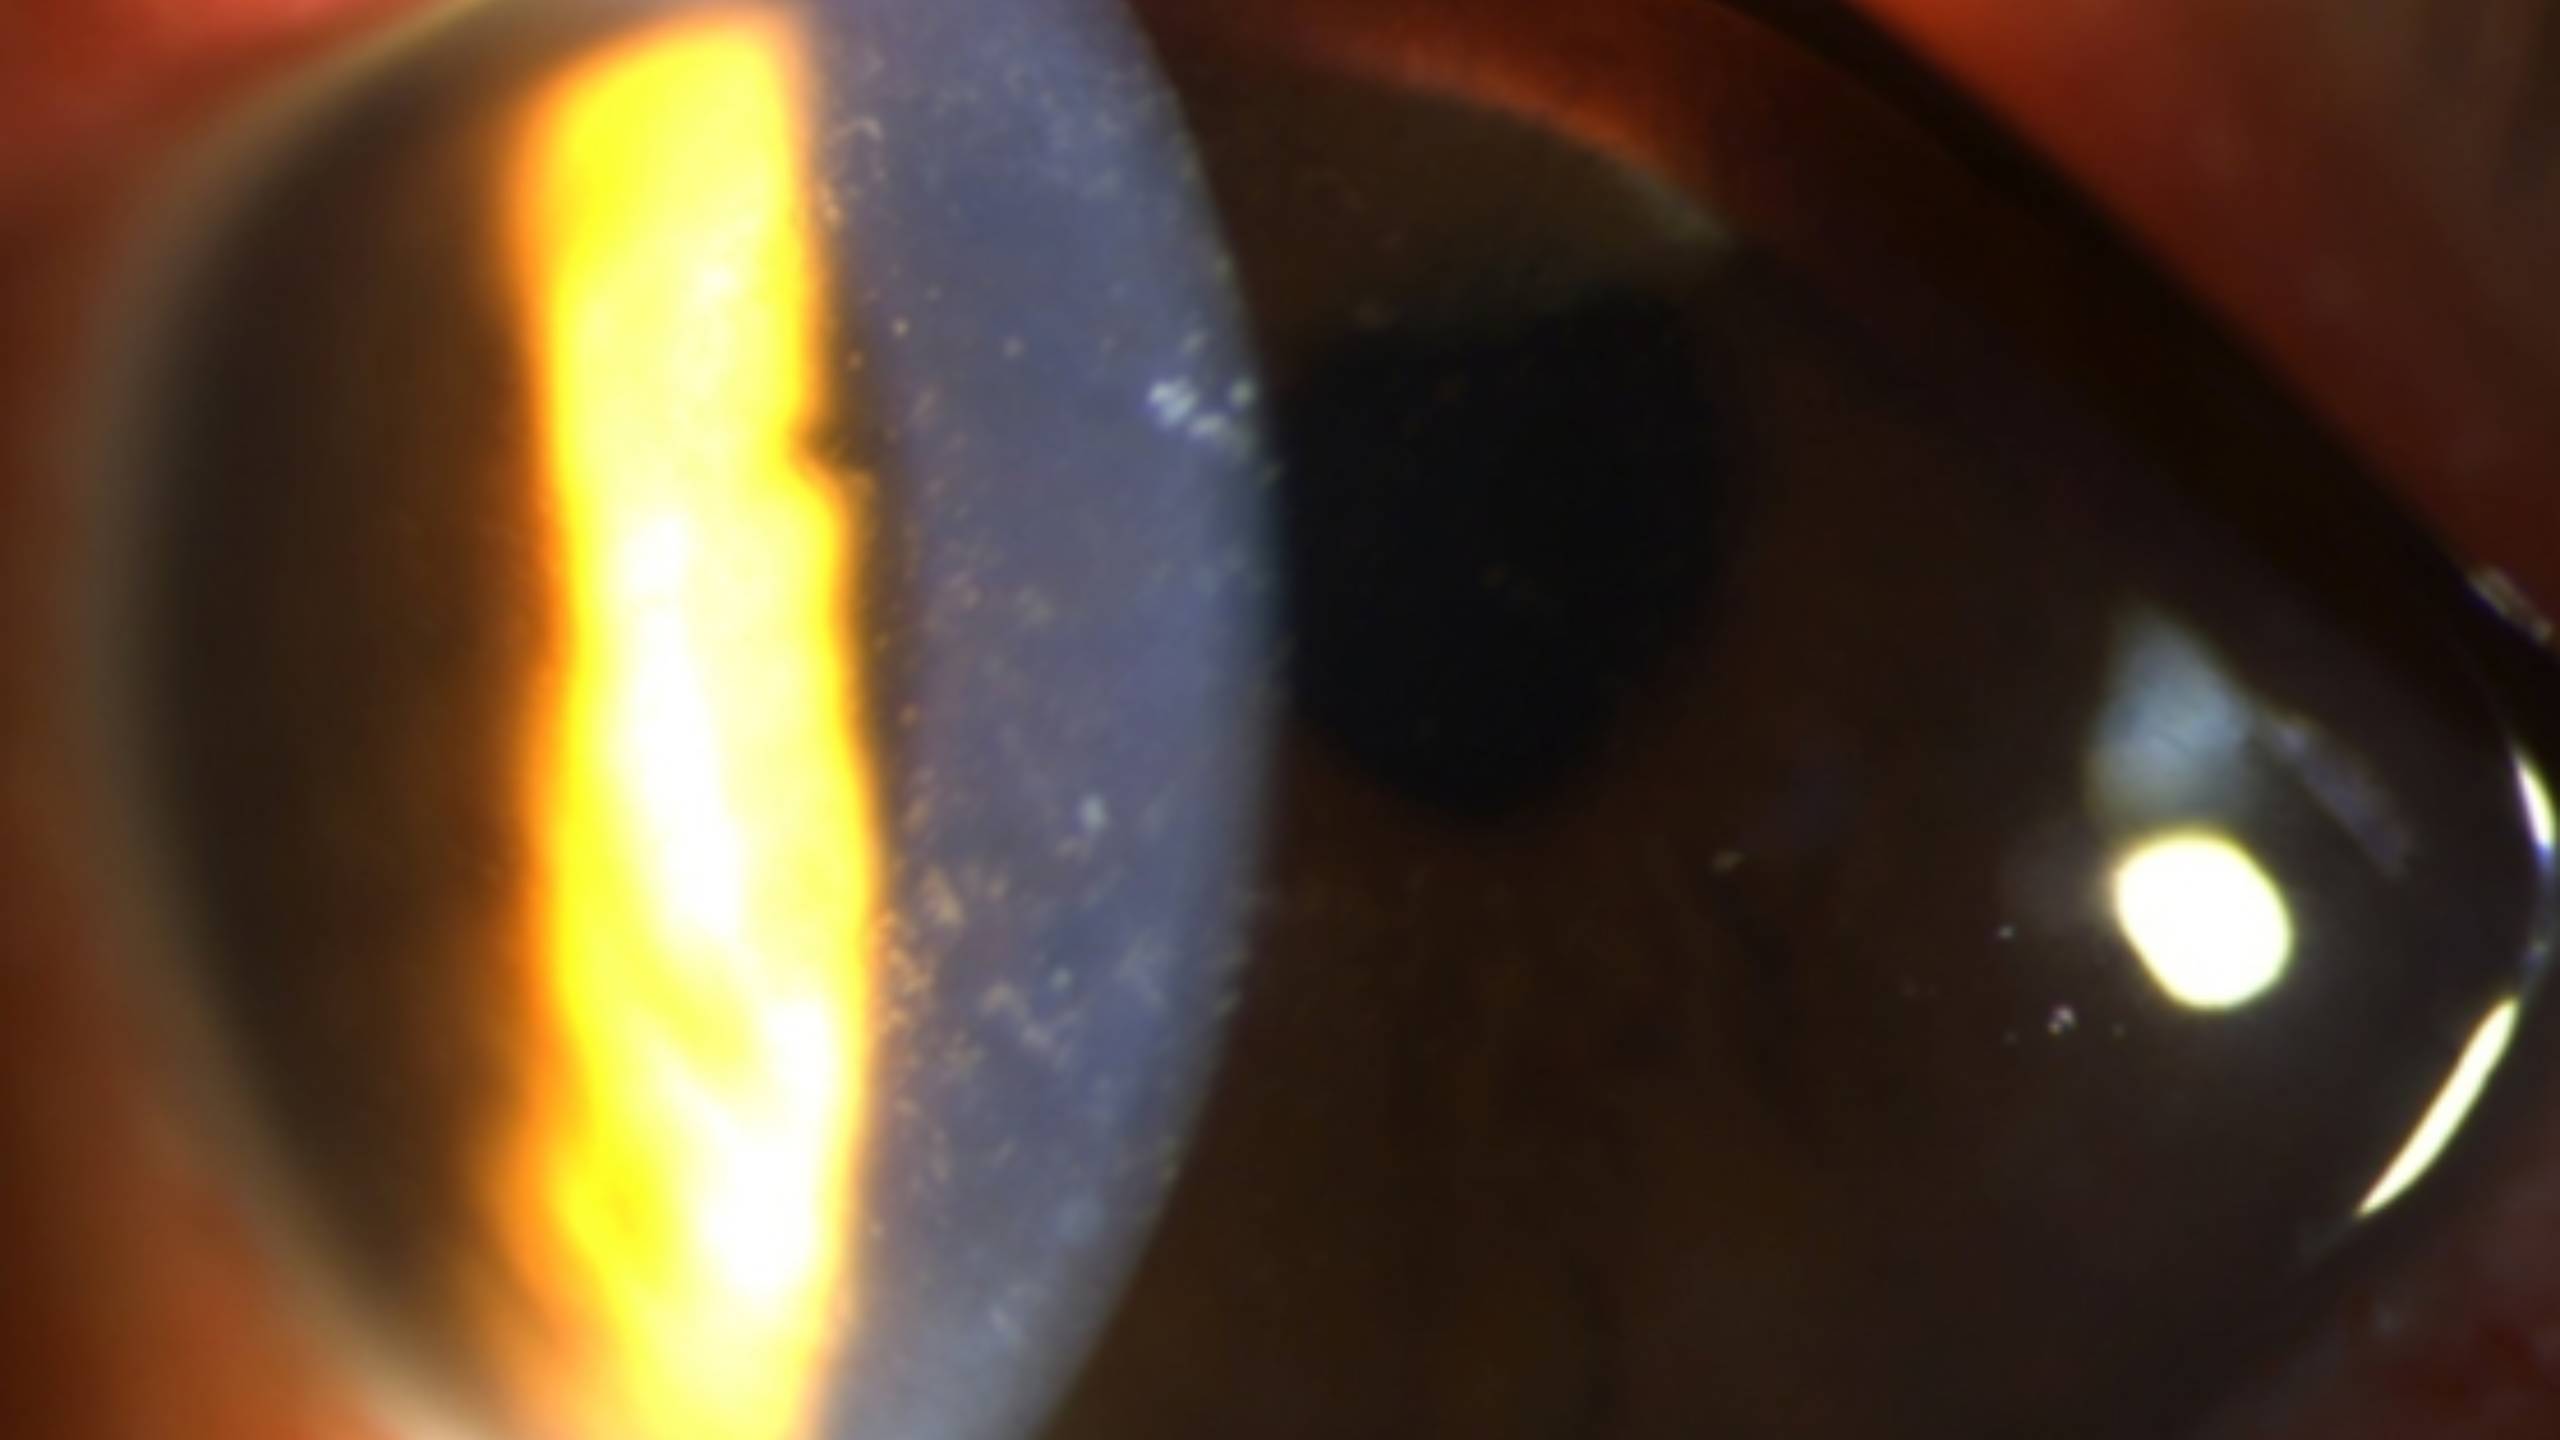

表皮型的症狀包括異物感、眼紅、畏光、視力減退、流淚、眼皮水腫等非特異症狀,可能有前房反應,通常是單眼,但也可能雙眼發生。表皮會有多個邊緣模糊點狀隆起,大小不一、形狀各異的病灶(圖一)。感覺是異物黏在角膜表面,以螢光染色後程度不一(圖二)。乍看之下不會覺得那是感染,而是角膜表皮沾染了什麼東西。用棉棒輕拭也可以去掉,因此更會愚弄醫師,覺得那根本不是感染;但拭除這些小白點後,第二天又在不同位置產生一樣的病灶。

(圖一)大小不一、形狀各異的病灶